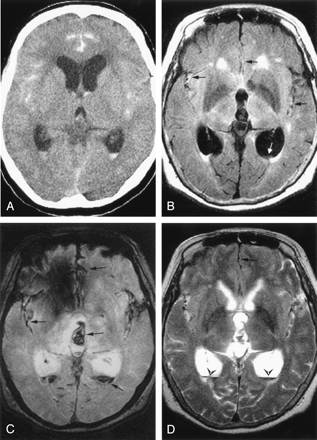

A 65-year-old woman had a sudden-onset headache. CT scan obtained 7.3 hours after the ictus showed SAH in the sylvian fissures and interhemispheric fissure as well as IVH in the 3rd and both lateral ventricles (Fig 1A). FLAIR images obtained 10.3 hours after the ictus showed the SAH as an area of mildly increased signal intensity relative to brain parenchyma and subtle IVH as area of mildly increased signal intensity relative to CSF (Fig 1B). GRE T2*-weighted images clearly showed the SAH and IVH as areas of decreased signal intensity (Fig 1C). FSE T2-weighted images also showed the IVH as area of decreased signal intensity in the lateral and 3rd ventricle but did not visualize the Sylvian SAH (Fig 1D). Preoperative noncontrast time-of-flight (TOF) MR angiography visualized a left anterior communicating artery aneurysm. An external ventricular drain (EVD) was inserted, and the aneurysm was clipped.

Case 1, a 65-year-old woman with hyperacute SAH and IVH due to a ruptured left anterior communicating artery aneurysm.

A, CT scan (7.3 hours postictus) shows an SAH and IVH in the both Sylvian fissures, the anterior interhemispheric fissure, and the occipital horns of both lateral ventricles.

B–D, MR images obtained 10.3 hours postictus. Axial FLAIR image (B) shows high signal intensity in the anterior interhemispheric fissure and both Sylvian fissures (black arrows). A layered area mildly increased signal intensity is evident in occipital horn of the left lateral ventricle (white arrow). Axial GRE T2*-weighted image (C) shows decreased signal intensity in the interhemispheric and both Sylvian fissures, 3rd ventricle, and occipital horns of both lateral ventricles (arrows). Axial fast spin-echo T2-weighted image (D) shows linear low signal intensity in the anterior interhemispheric fissure (arrow) and blood-CSF layered pattern of the IVH (arrowheads) in the occipital horns of both lateral ventricles.